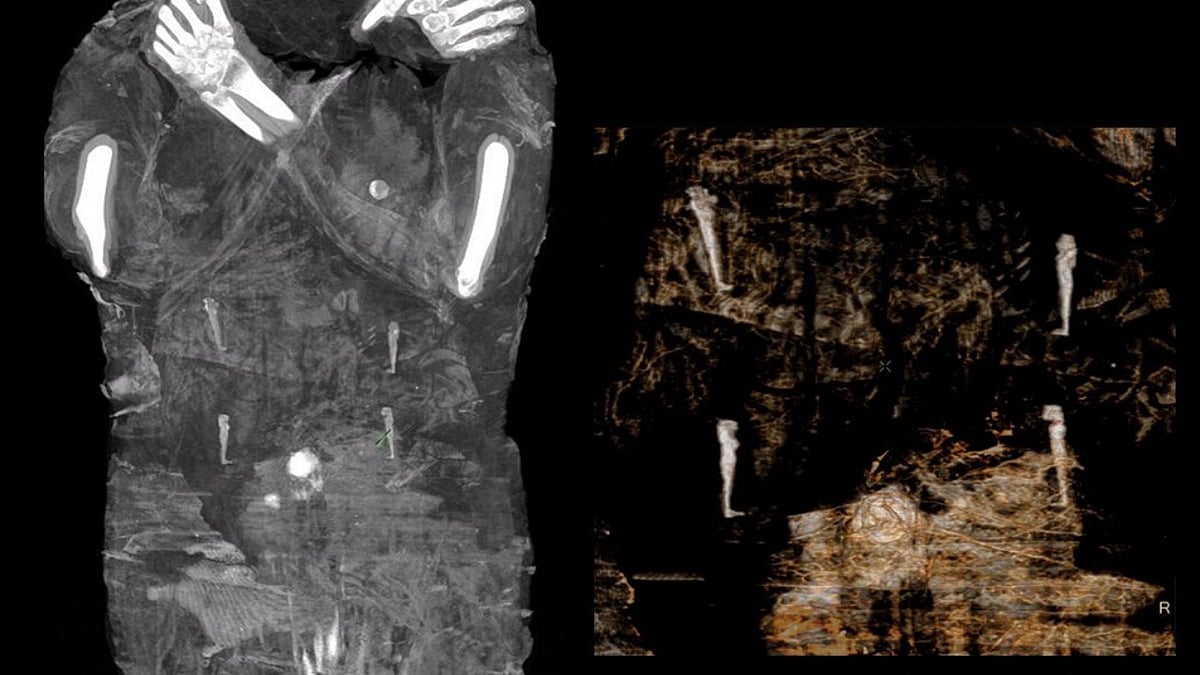

This Handout picture made available by the "Warsaw Mummy Project" on April 29, 2021 shows X-Ray images of the pregnant Egyptian mummy taken in 2015 at a medical centre in Otwock near Warsaw, Poland. | AFP Photo

Polish researchers examining an ancient Egyptian mummy that they expected to be a male priest were surprised when X-rays and computer tests revealed instead it was a mummy of a woman who had been seven months pregnant.

"When we saw the little foot and then the little hand (of the fetus), we were really shocked." They estimated the woman was between 20 and 30 years old and said the size of the baby's skull suggested she was 26 to 28 weeks pregnant.